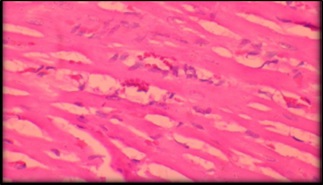

GroupI: Histology of heart showed normal architectural features(Fig.1)

Figure 1:Group Is howing normal myocardial fibres and artitecture (40x)